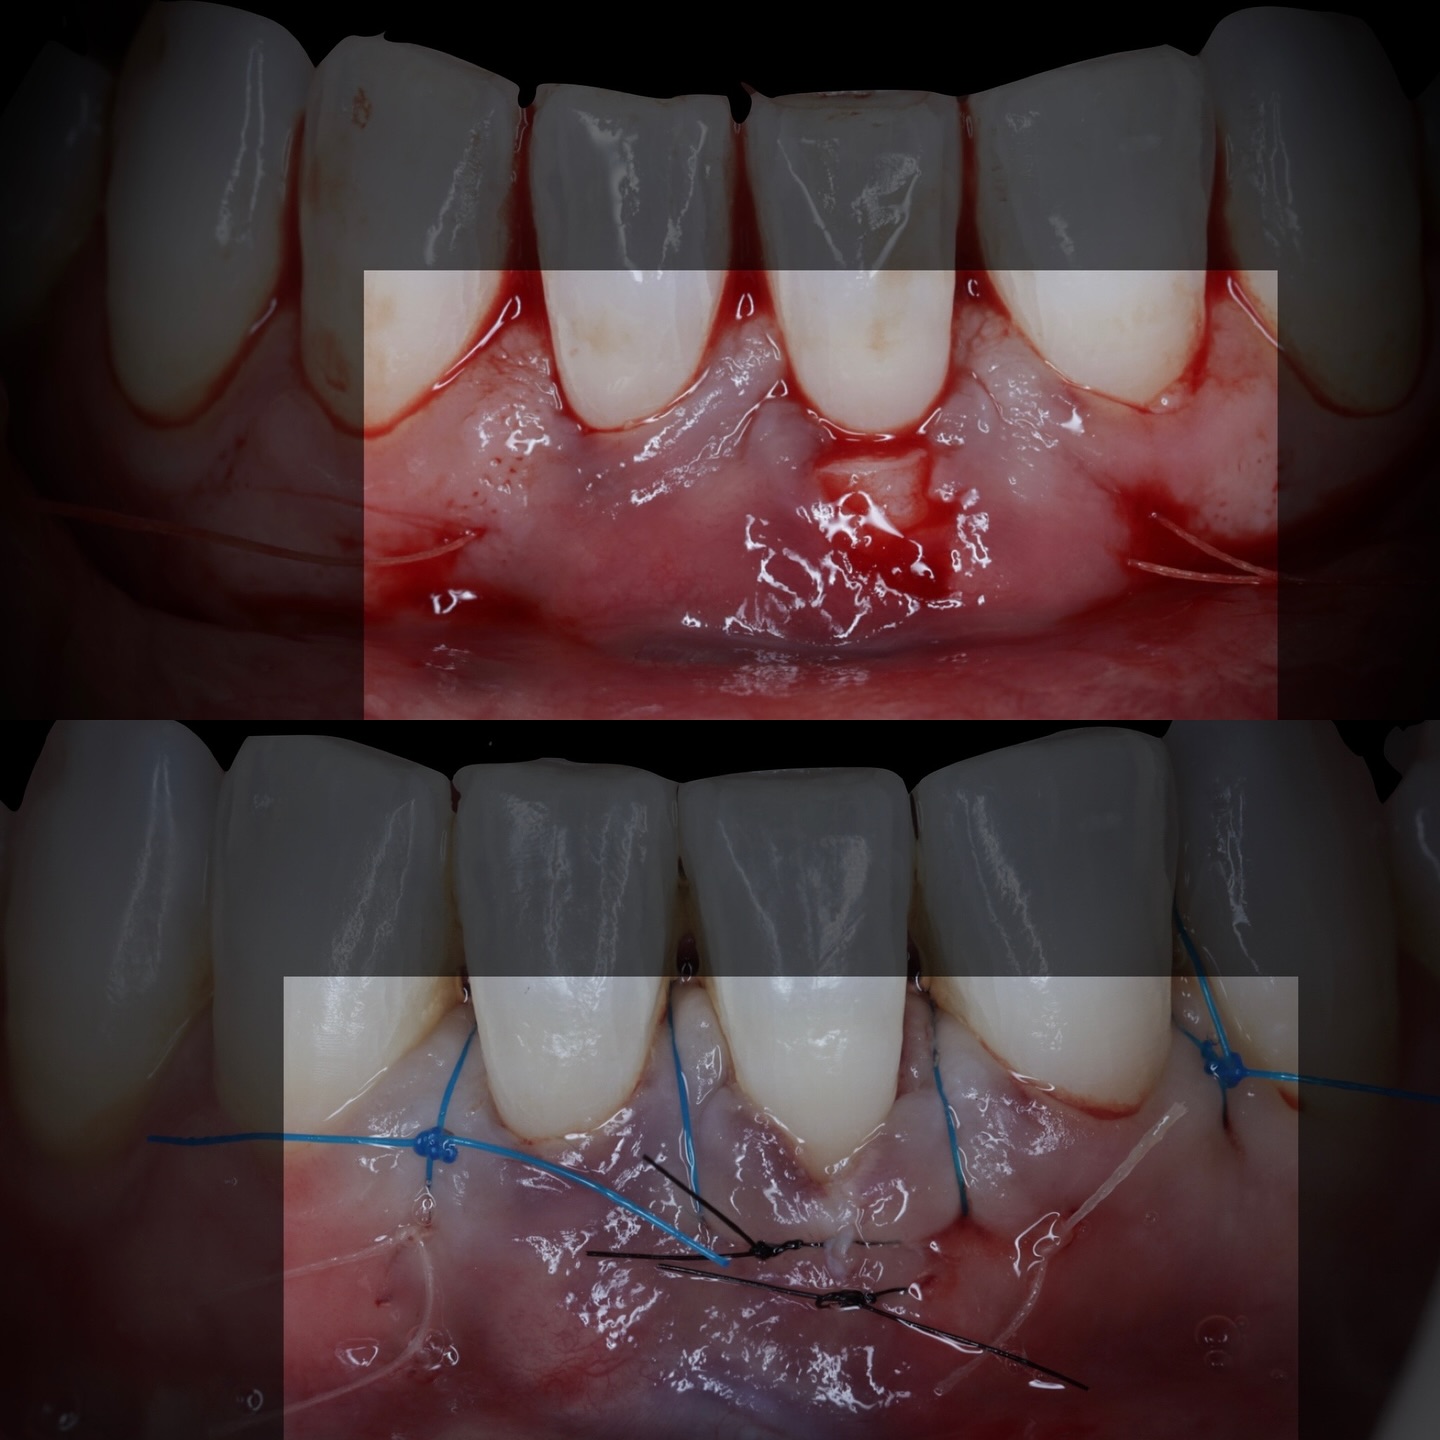

Durante una mañana, asistirás a una Cirugía Mucogingival de recubrimiento radicular de recesiones múltiples en IV y V sextante (36 a 43).

Gracias al uso del microscopio y a la proyección en tiempo real en pantalla, verás exactamente lo mismo que veo yo durante la cirugía, sin tener que estar

Se realizará todo el procedimiento con un microscopio operatorio, lo que permite al alumno ver toda la cirugía en directo en una pantalla en la sala de cirugía.

La formación comenzará con la presentación del caso clínico que se abordará durante el curso, seguida de una cirugía en directo, que permitirá observar paso a paso el procedimiento y la toma de decisiones clínicas. Durante la jornada se profundizará en los conceptos biológicos aplicados a

Durante una mañana, asistirás a una Cirugía Mucogingival de recubrimiento radicular de una recesión unitaria en 31 con frenillo asociado. Gracias al uso del microscopio y a la proyección en tiempo real en pantalla, verás exactamente lo mismo que veo yo durante la cirugía, sin tener que estar